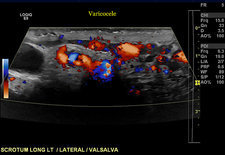

Απόλυτες ενδείξεις διόρθωσης κιρσοκήλης αποτελούν

- Κιρσοκήλη σε συνδυασμό με υπογονιμότητα που δεν μπορεί να αποδοθεί σε άλλο αίτιο

- Σταδιακή μείωση του όγκου του σύστοιχου όρχεος σε παιδιά και εφήβους με κιρσοκήλη